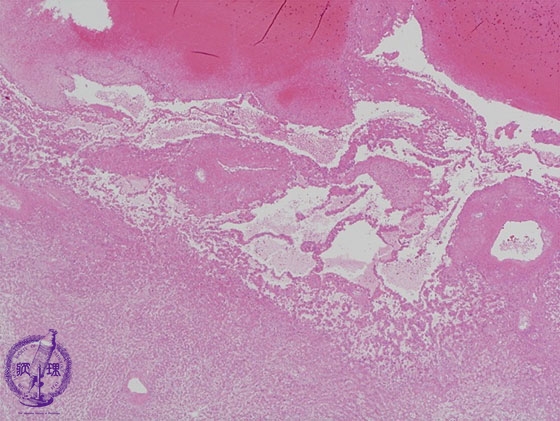

- ★(14)Angiosarcoma of the liver

Microscopic image (HE stain, low power): The boundary (yellow dashed line) between tumor and non-neoplastic liver is unclear.